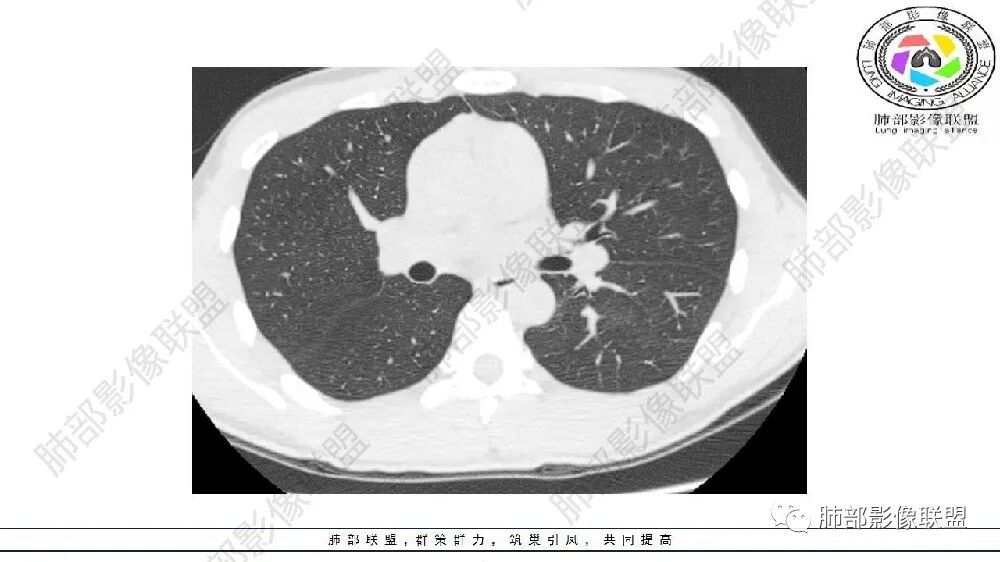

左肺下叶病变气体潴留,血管增粗,体积缩小,慢性炎遗留表现,考虑局部反复感染,气道通畅,考虑血管病变,肺静脉畸形,肺隔离症?

左肺下叶多发囊腔、斑片、索条(粗大扭曲的血管?)降主动脉左侧有血管影?首先考虑肺隔离症,建议增强扫描,鉴别囊腺瘤样畸形

左肺下叶多发囊腔,粗大血管影,隔离征可能,鉴别气道畸形。

年轻男性,左肺下叶肺动脉明显增粗特点(与对侧比较,降主动脉旁胸膜下分布粗大血管征、左肺下叶肺气囊腔和磨玻璃影,首选肺隔离征,与血管畸形鉴别,病理生理特点:体循环异常分支(压力高)与左肺下叶肺动脉成异常交通。血管血流倒灌左肺下叶表现。

可见囊状影、管状影,附近血管明显增粗,似乎与肺动脉不相连

1、需要明确血管与主动脉关系,如果相连--隔离症

主要观察左下叶病灶,应该是做过手术或明确了血管与主动脉关系,就目前的表现而言还是更支持隔离:肺动脉、支气管分支似乎没进入病灶区,这是隔离或体动脉供血的特点。囊腺瘤样畸形,按理肺动脉及支气管照样进入这个区域才对;需要重建观察这些血管、支气管才好明确